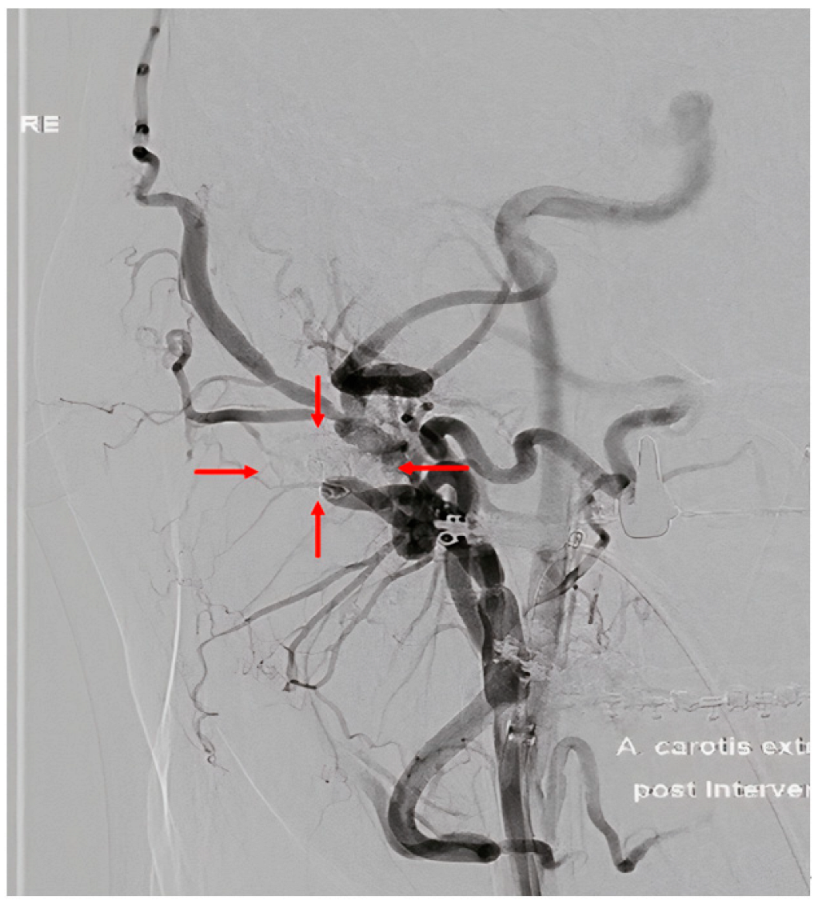

2. Case Report